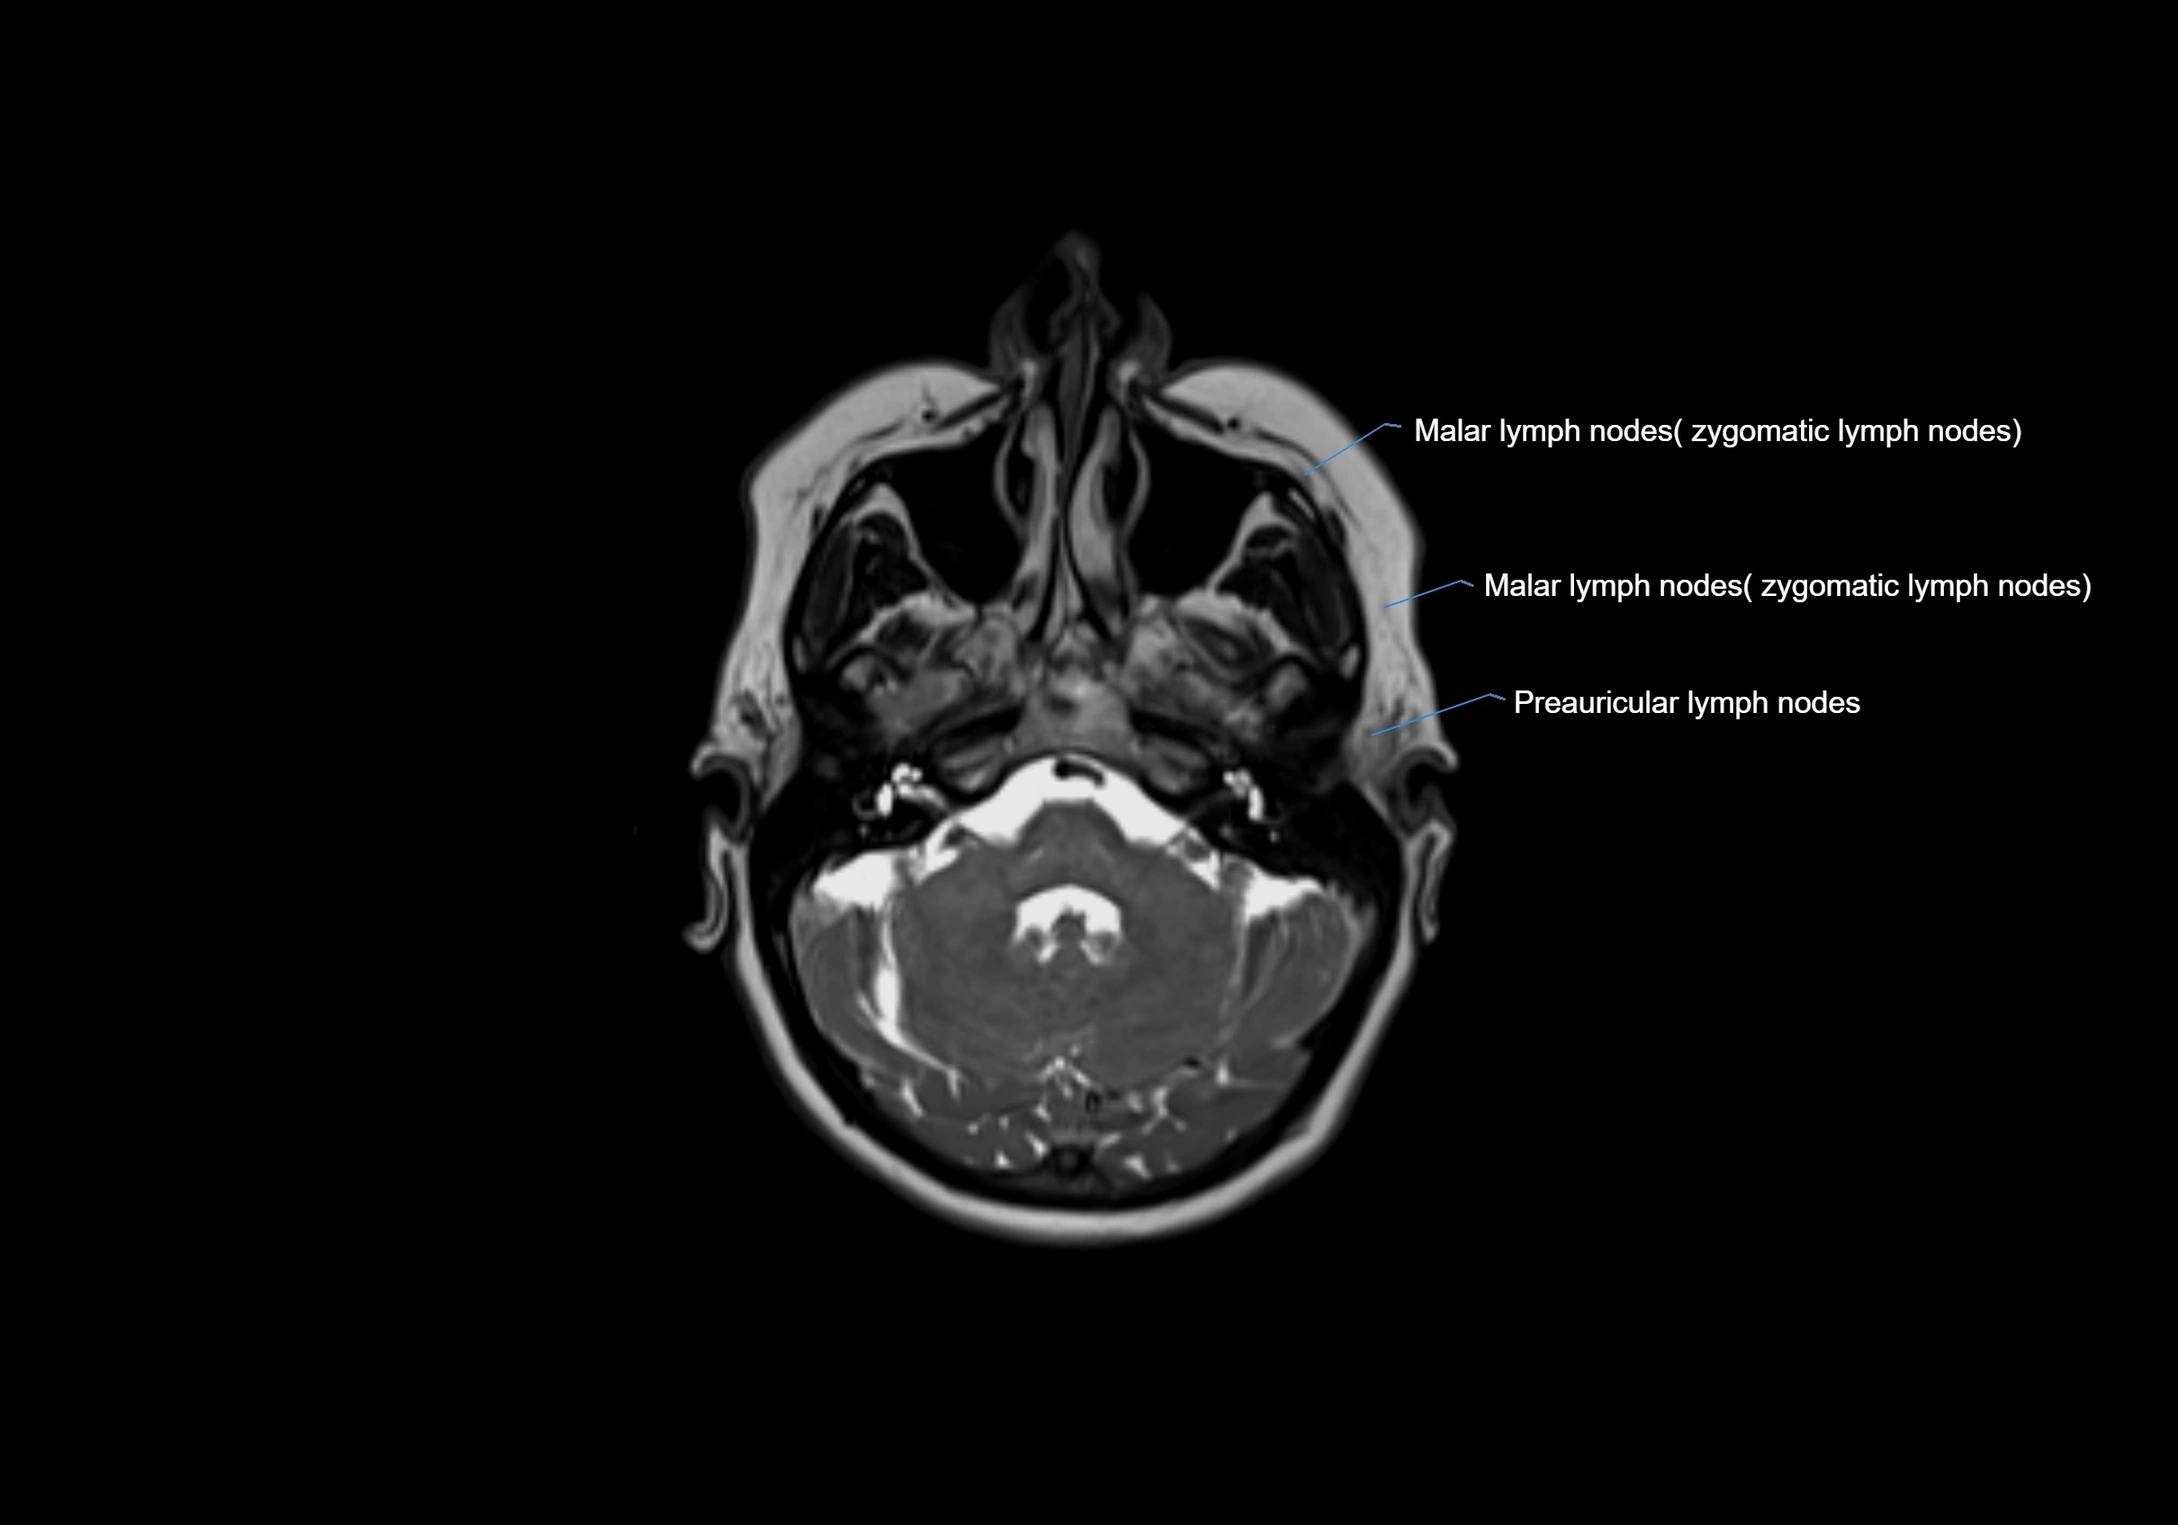

• Found along primary lymph node chains, including preauricular, submandibular, parotid, and occipital regions

MRI Appearance

T2-weighted images:

• Nodes show intermediate signal, with surrounding fat bright

• Useful for detecting edema, inflammation, or infiltration

• Fatty hilum may appear slightly hyperintense relative to cortex

image